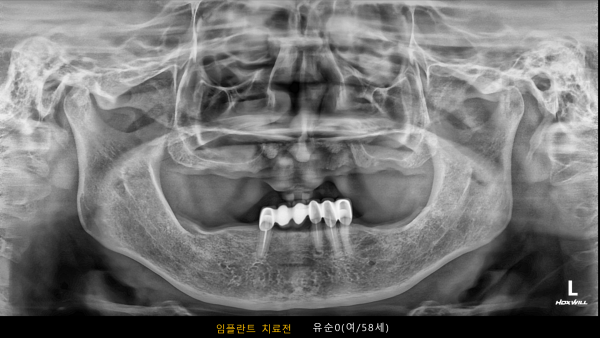

고난도 센터 | 여) 58세